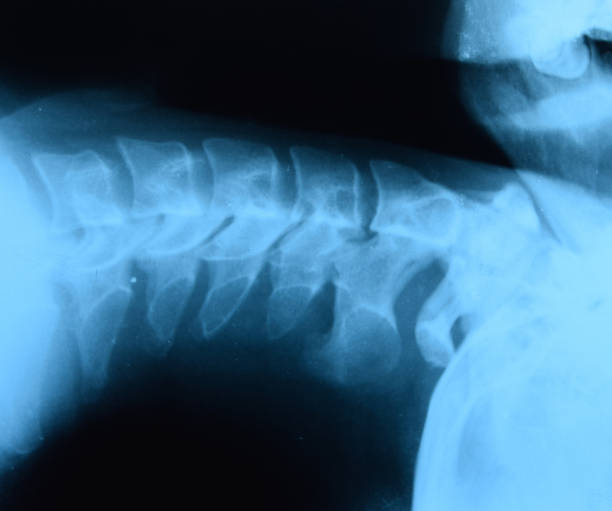

척추에서 나타나는 만성적인 관절염을 강직성 척추염이라고 합니다. 강직성 척추염이라는 말의 의미를 생각해보면 강직은 말 그대로 뻗뻗해지거나 굳어버리는 것을 의미하고 척추염은 척추에 염증이 생겼다는 의미기 때문에 증상 자체도 쉽게 유측할 수 있습니다. 해당 증상은 척추 외에도 우리 몸 전체인 엉덩이, 무릎, 어깨 등에도 염증을 유발할 수 있기 때문에 관리를 초기부터 필요합니다.

척추가 경직되고 염증이 발생하는 강직성 척추염의 염증의 형태는 통증, 부종, 빨간 붓기를 동반하며 이 염증은 척추를 굳게 만들기 때문에 움직임이 둔해지고 경직됩니다. 가볍게 증상이 나타날 수 있지만 느끼지 못한다면 빠르게 치료를 시작해야만 척추의 변형을 막을 수 있습니다.

강직성 척추염 증상은 허리가 굳어가는 듯한 느낌을 먼저 받게 되며 특히 아침에 기상시에 굳어있는 느낌을 강하게 받을 수 있으나 운동이나 가벼운 활동을 하면 증상이 완화될 수 있습니다. 이 때는 3개월 이상 굳은 느낌이 지속되거나 평소와 다르게 같은 자세로 앉아있거나 서있기 어려운 경우, 통증이 허리 쪽에 그치는 것이 아니라 발바닥, 뒤꿈치, 갈비뼈, 가슴 등 다른 부위에서도 통증을 유발할 수 있으며 이러한 증상들이 동반된 경우 강직성 척추염을 의심할 수 있으며 운동 후에 증상이 완화된다면 강직성 척추염일 가능성이 큽니다.